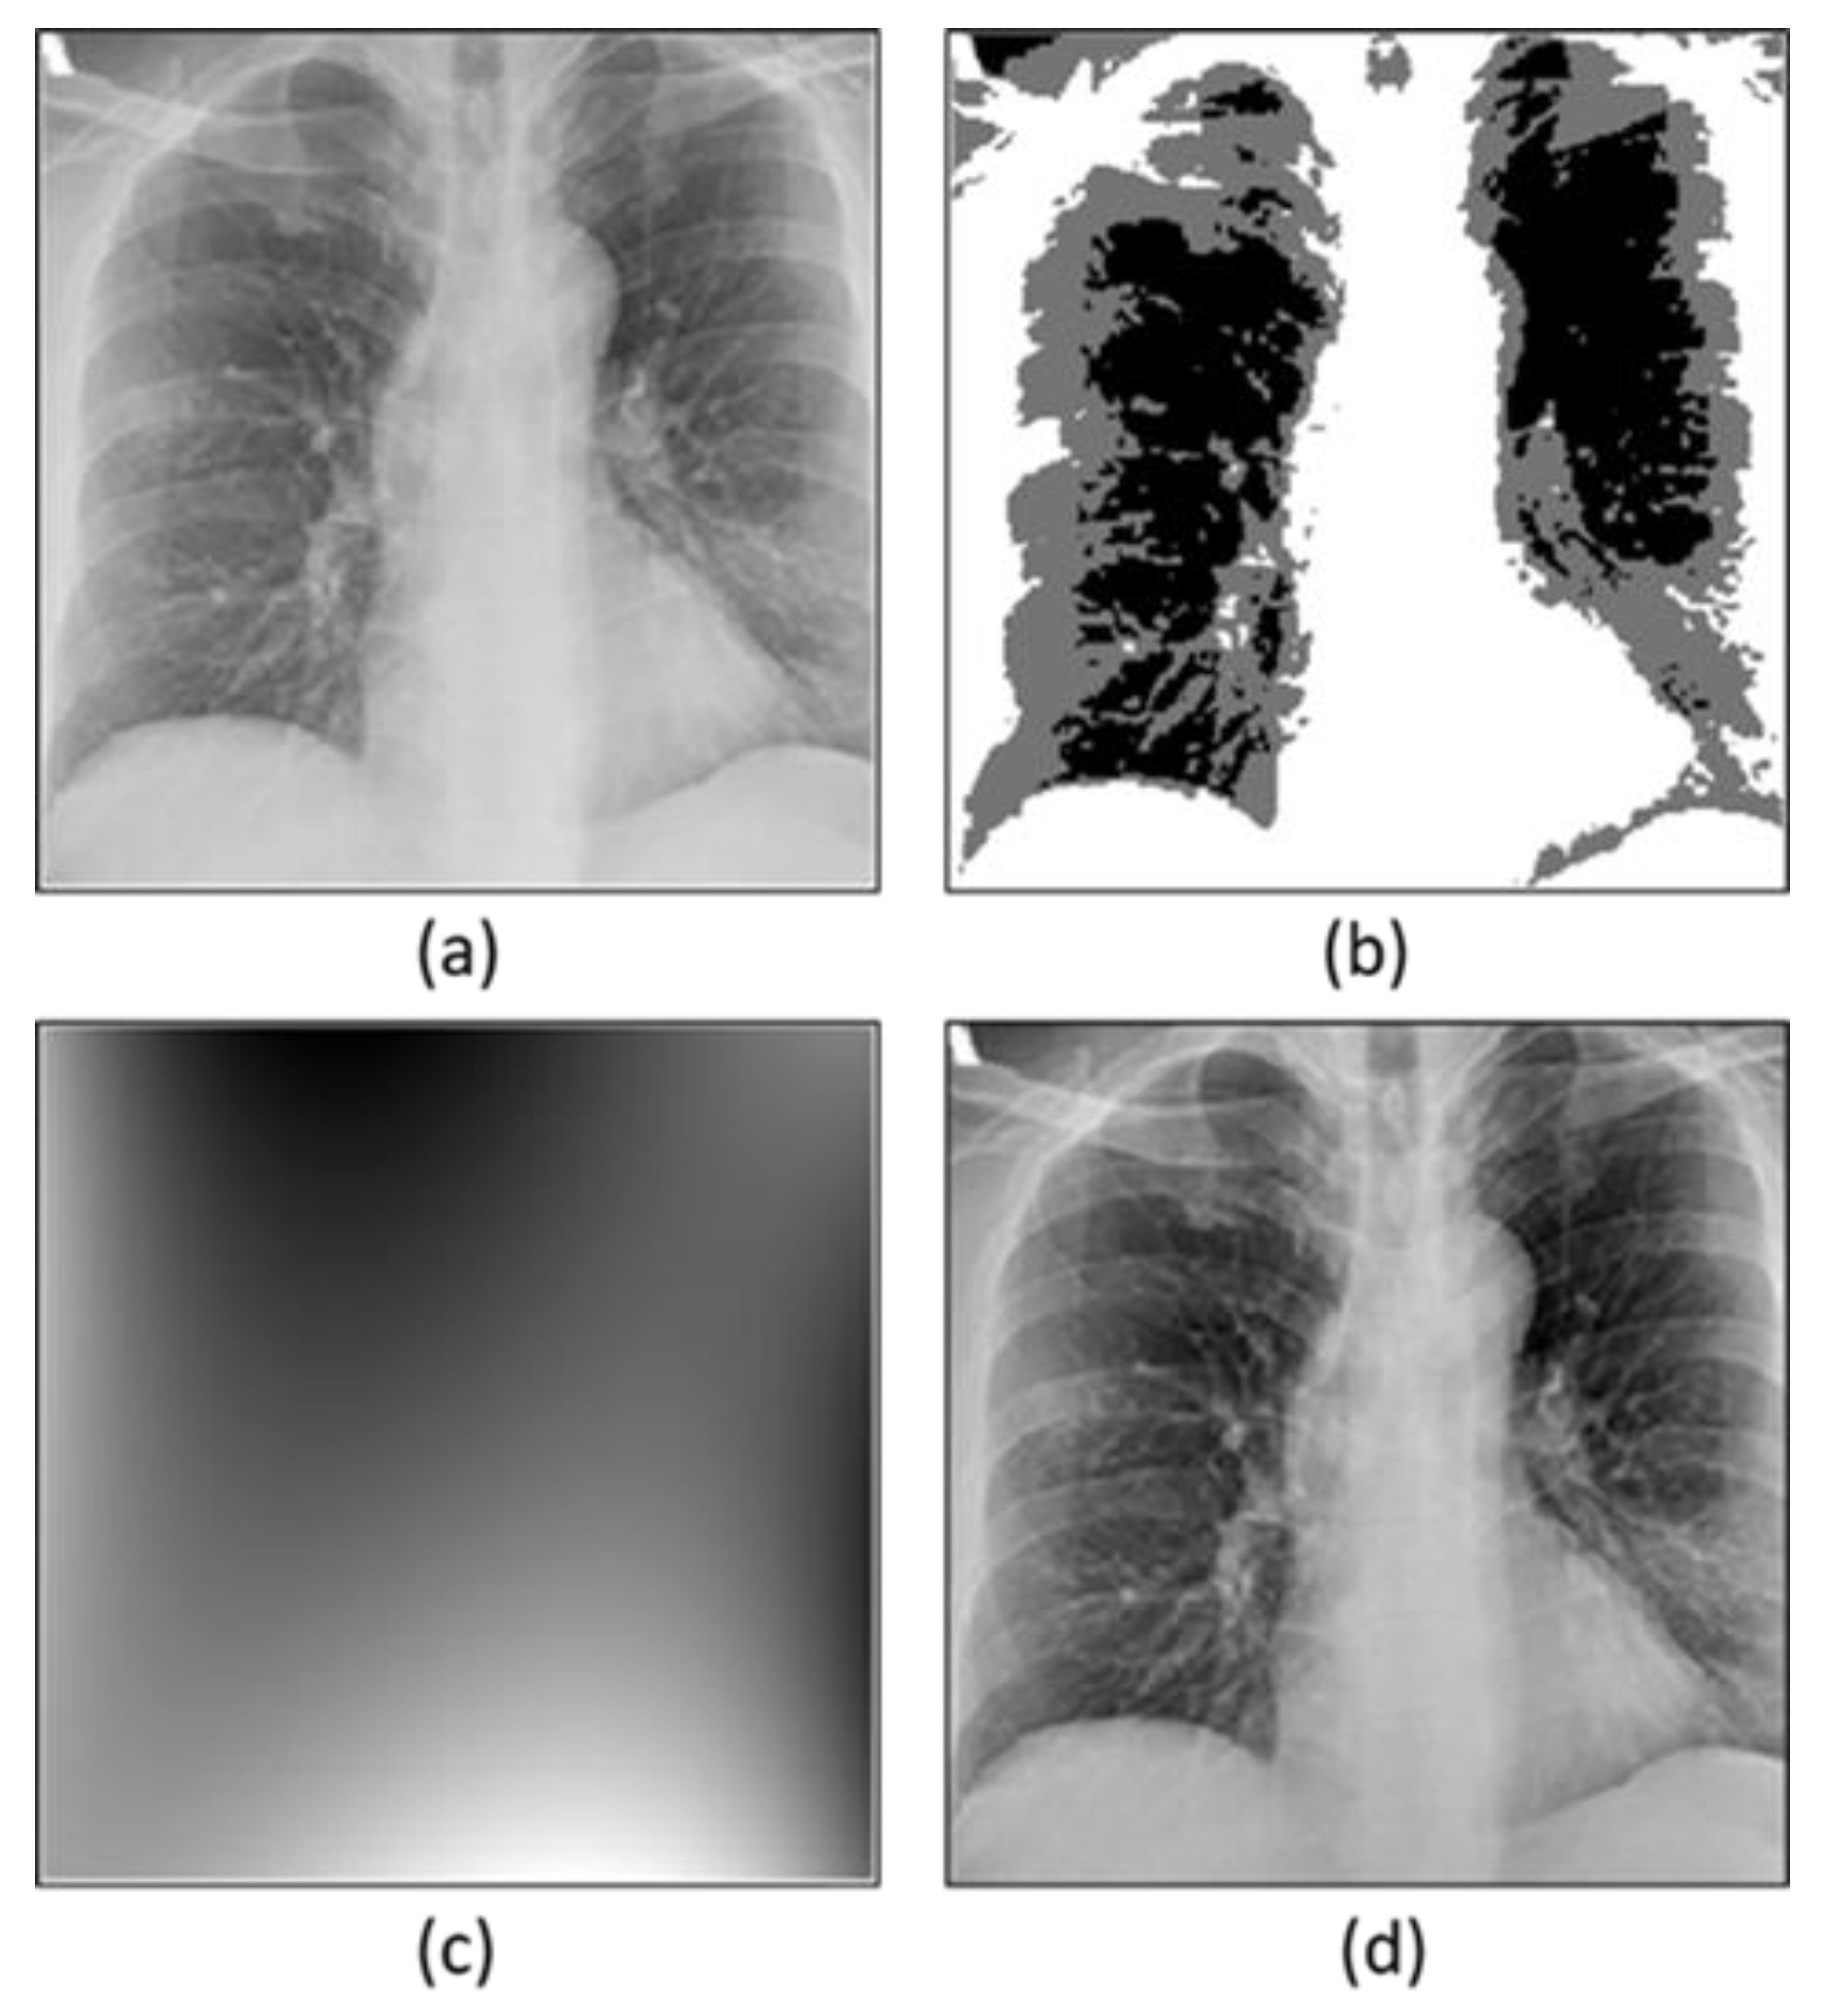

- Preprocessing of the X-ray images by performing intensity inhomogeneity correction to obtain the optimal performance of the model and correct the image intensity.

3.2.1. Bias Field Correction